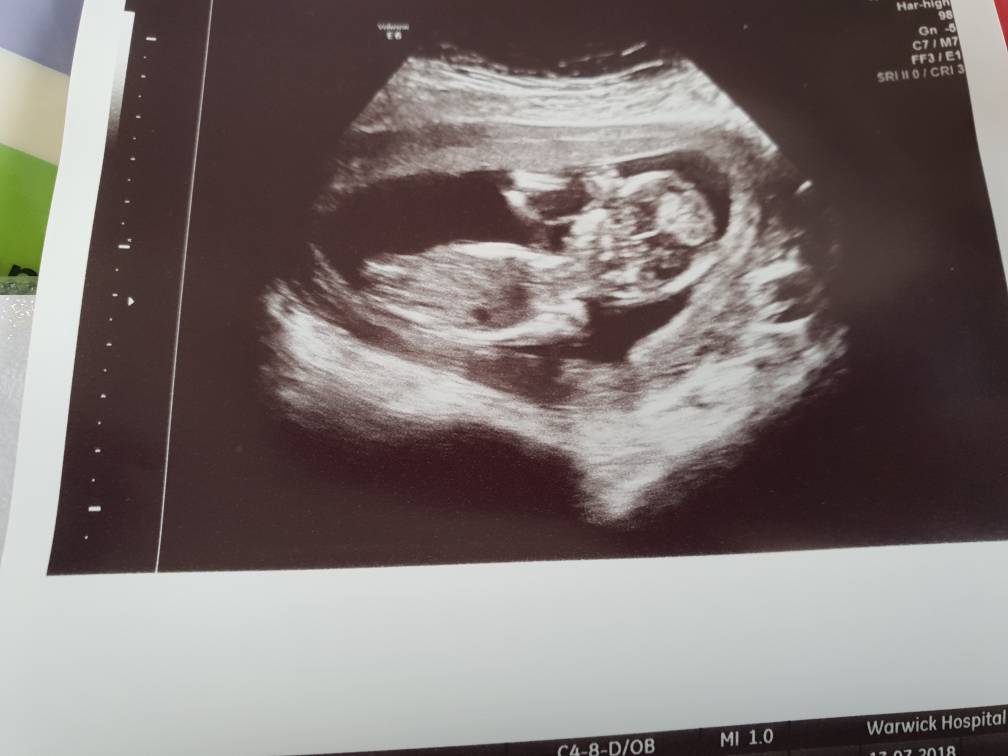

Update at 13.2 [emoji4]Attachment 39899Attachment 39900Attachment 39901